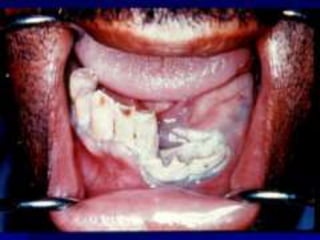

 ---Osteoradionecrosis isa possible complication following radiotherapy where an area of bone does not heal from irradiation. Irradiation of bones causes damage to osteocytes and impairs the blood supply. The affected hard tissues become hypovascular (reduced number of blood vessels), hypocellular (reduced number of cells) and hypoxic (low levels of oxygen). Osteoradionecrosis usually occurs in the mandible, and causes chronic pain and surface ulceration. Prevention of osteradionecrosis is part of the reason all teeth of questionable prognosis are removed before the start of a course of radiotherapy

 Treatment ofosteoradionecrosis  1-Surgery  This means removing dead or infected tissue from around a wound. Dead, or necrotic, bone may also need to be removed. This is called sequestrectomy. This may include microvascular reconstructive surgery to restore blood flow to the area. Bone grafts may be needed to replace the sections of the jawbone that are removed. Soft tissue grafts can be used to replace muscle and other tissues that have been removed. You may also need dental implants if teeth are removed.